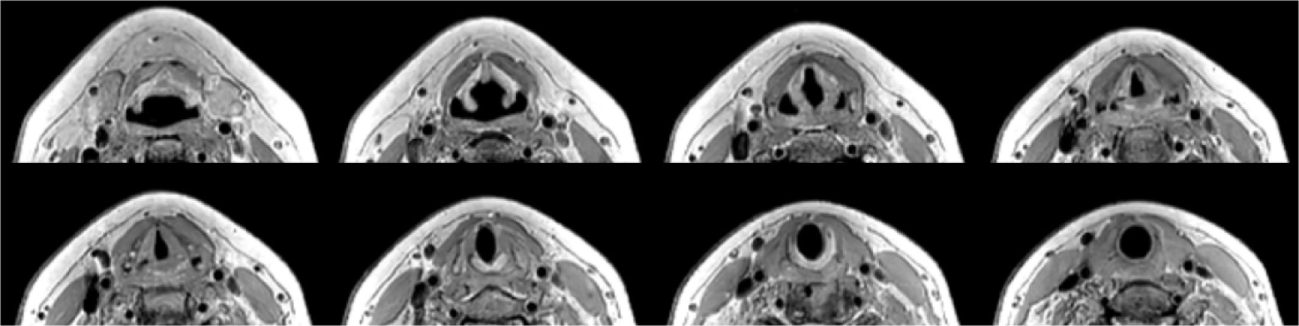

With the dedicated larynx coil, the entire length of the larynx can be covered and also the penetration depth is more than sufficient for imaging the full larynx. In total, 11 volunteers have been scanned with this setup, showing similar image quality for all volunteers. An example of the field of view is shown is shown in Figure 5.

Figure 5

T1 TSE 1.0 mm isotropic scan with parameters as in Table 1. A selection of eight out of 40 slices ranging from aryepiglottic fold to subglottis on a healthy volunteer showing depth of penetration far beyond the larynx.